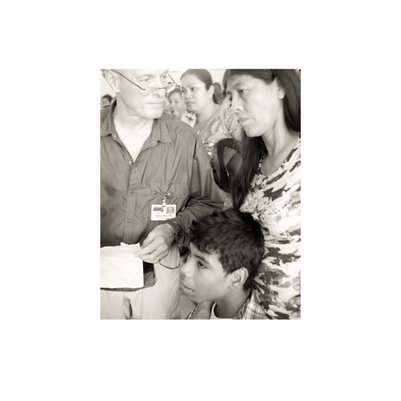

Darkness into the Light. In 2012, The Amazon Project gave eye care to nearly 6000 patients within a 200 kilometer radius of their base in Leticia, Colombia.